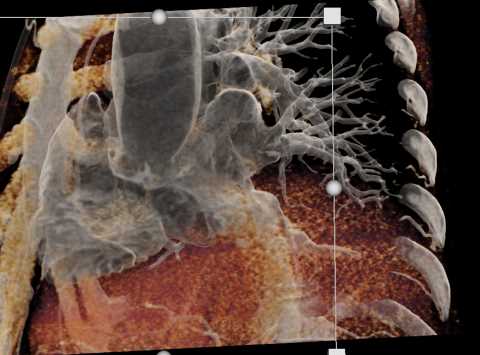

Primary Spindle Cell Carcinoma of the Right Ventricle